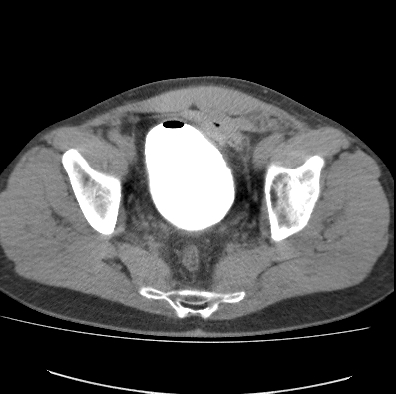

What Type of examination is this?

CT cystogram

Case courtesy of Dr Roberto Schubert, Radiopaedia.org, rID: 14924